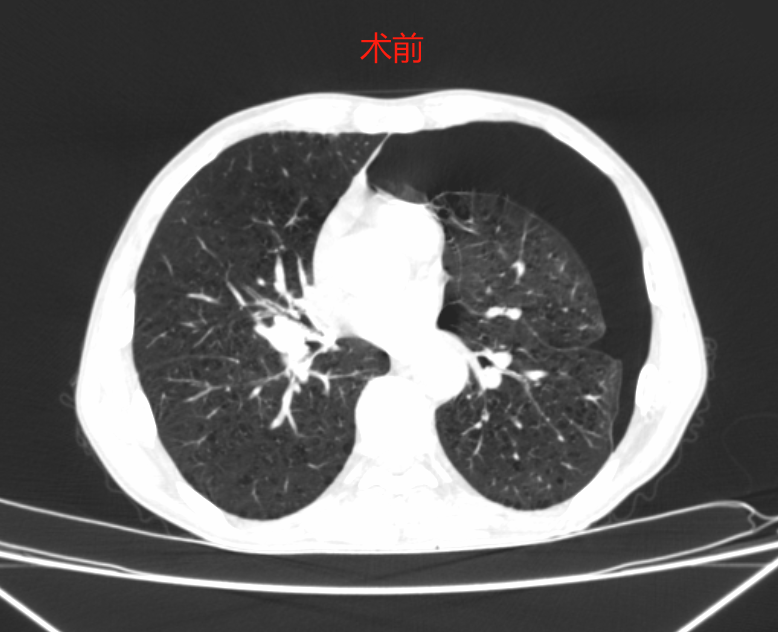

吳華副主任醫(yī)師接診后,為陳大叔詳細檢查,結(jié)合CT檢查提示左側(cè)氣胸,肺組織壓縮達50%以上,合并有雙肺肺氣腫、肺大泡。初步診斷為肺大泡破裂引起自發(fā)性氣胸。

術(shù)前,通過胸外科團隊問病查體、仔細閱片、綜合利用CT影像資料詳細評估了患者的病情,制定了胸腔鏡微創(chuàng)手術(shù)方案。